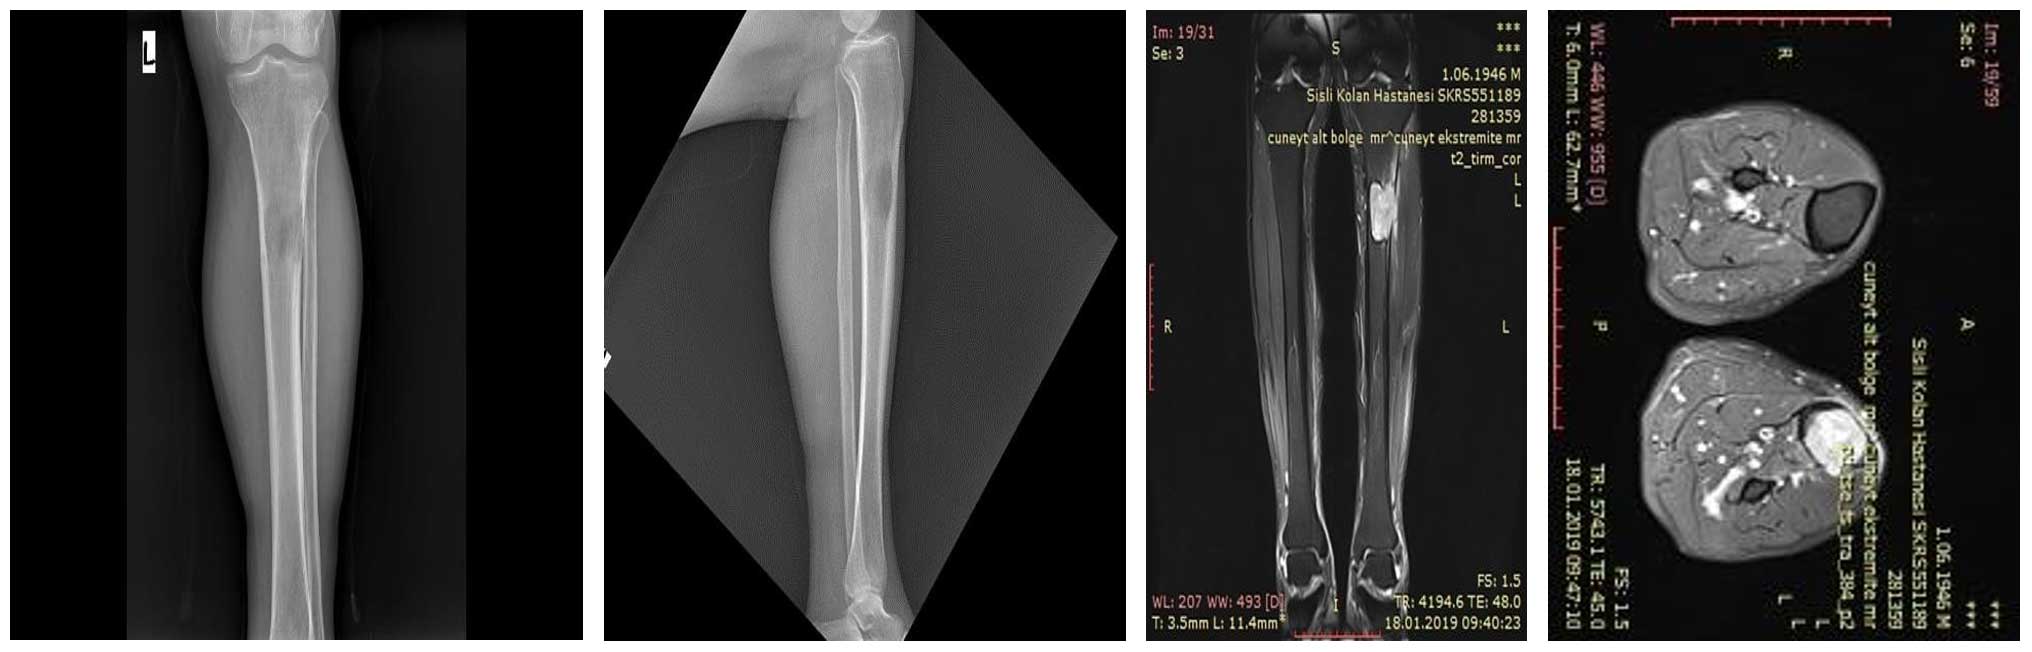

Görüntülemede sol proksimal tibia metastazı ve kırık riski saptandı

Sol proksimal tibia kemiğinde akciğer kanseri metastazına bağlı impending (yaklaşan) patolojik kırık riski

Ameliyat Öncesi: Röntgen ve MR’da tibia üst uçta kemiğin dış kısmını harabiyete uğratan ve kırık riski oluşturan metastaz odağı görülmekte.